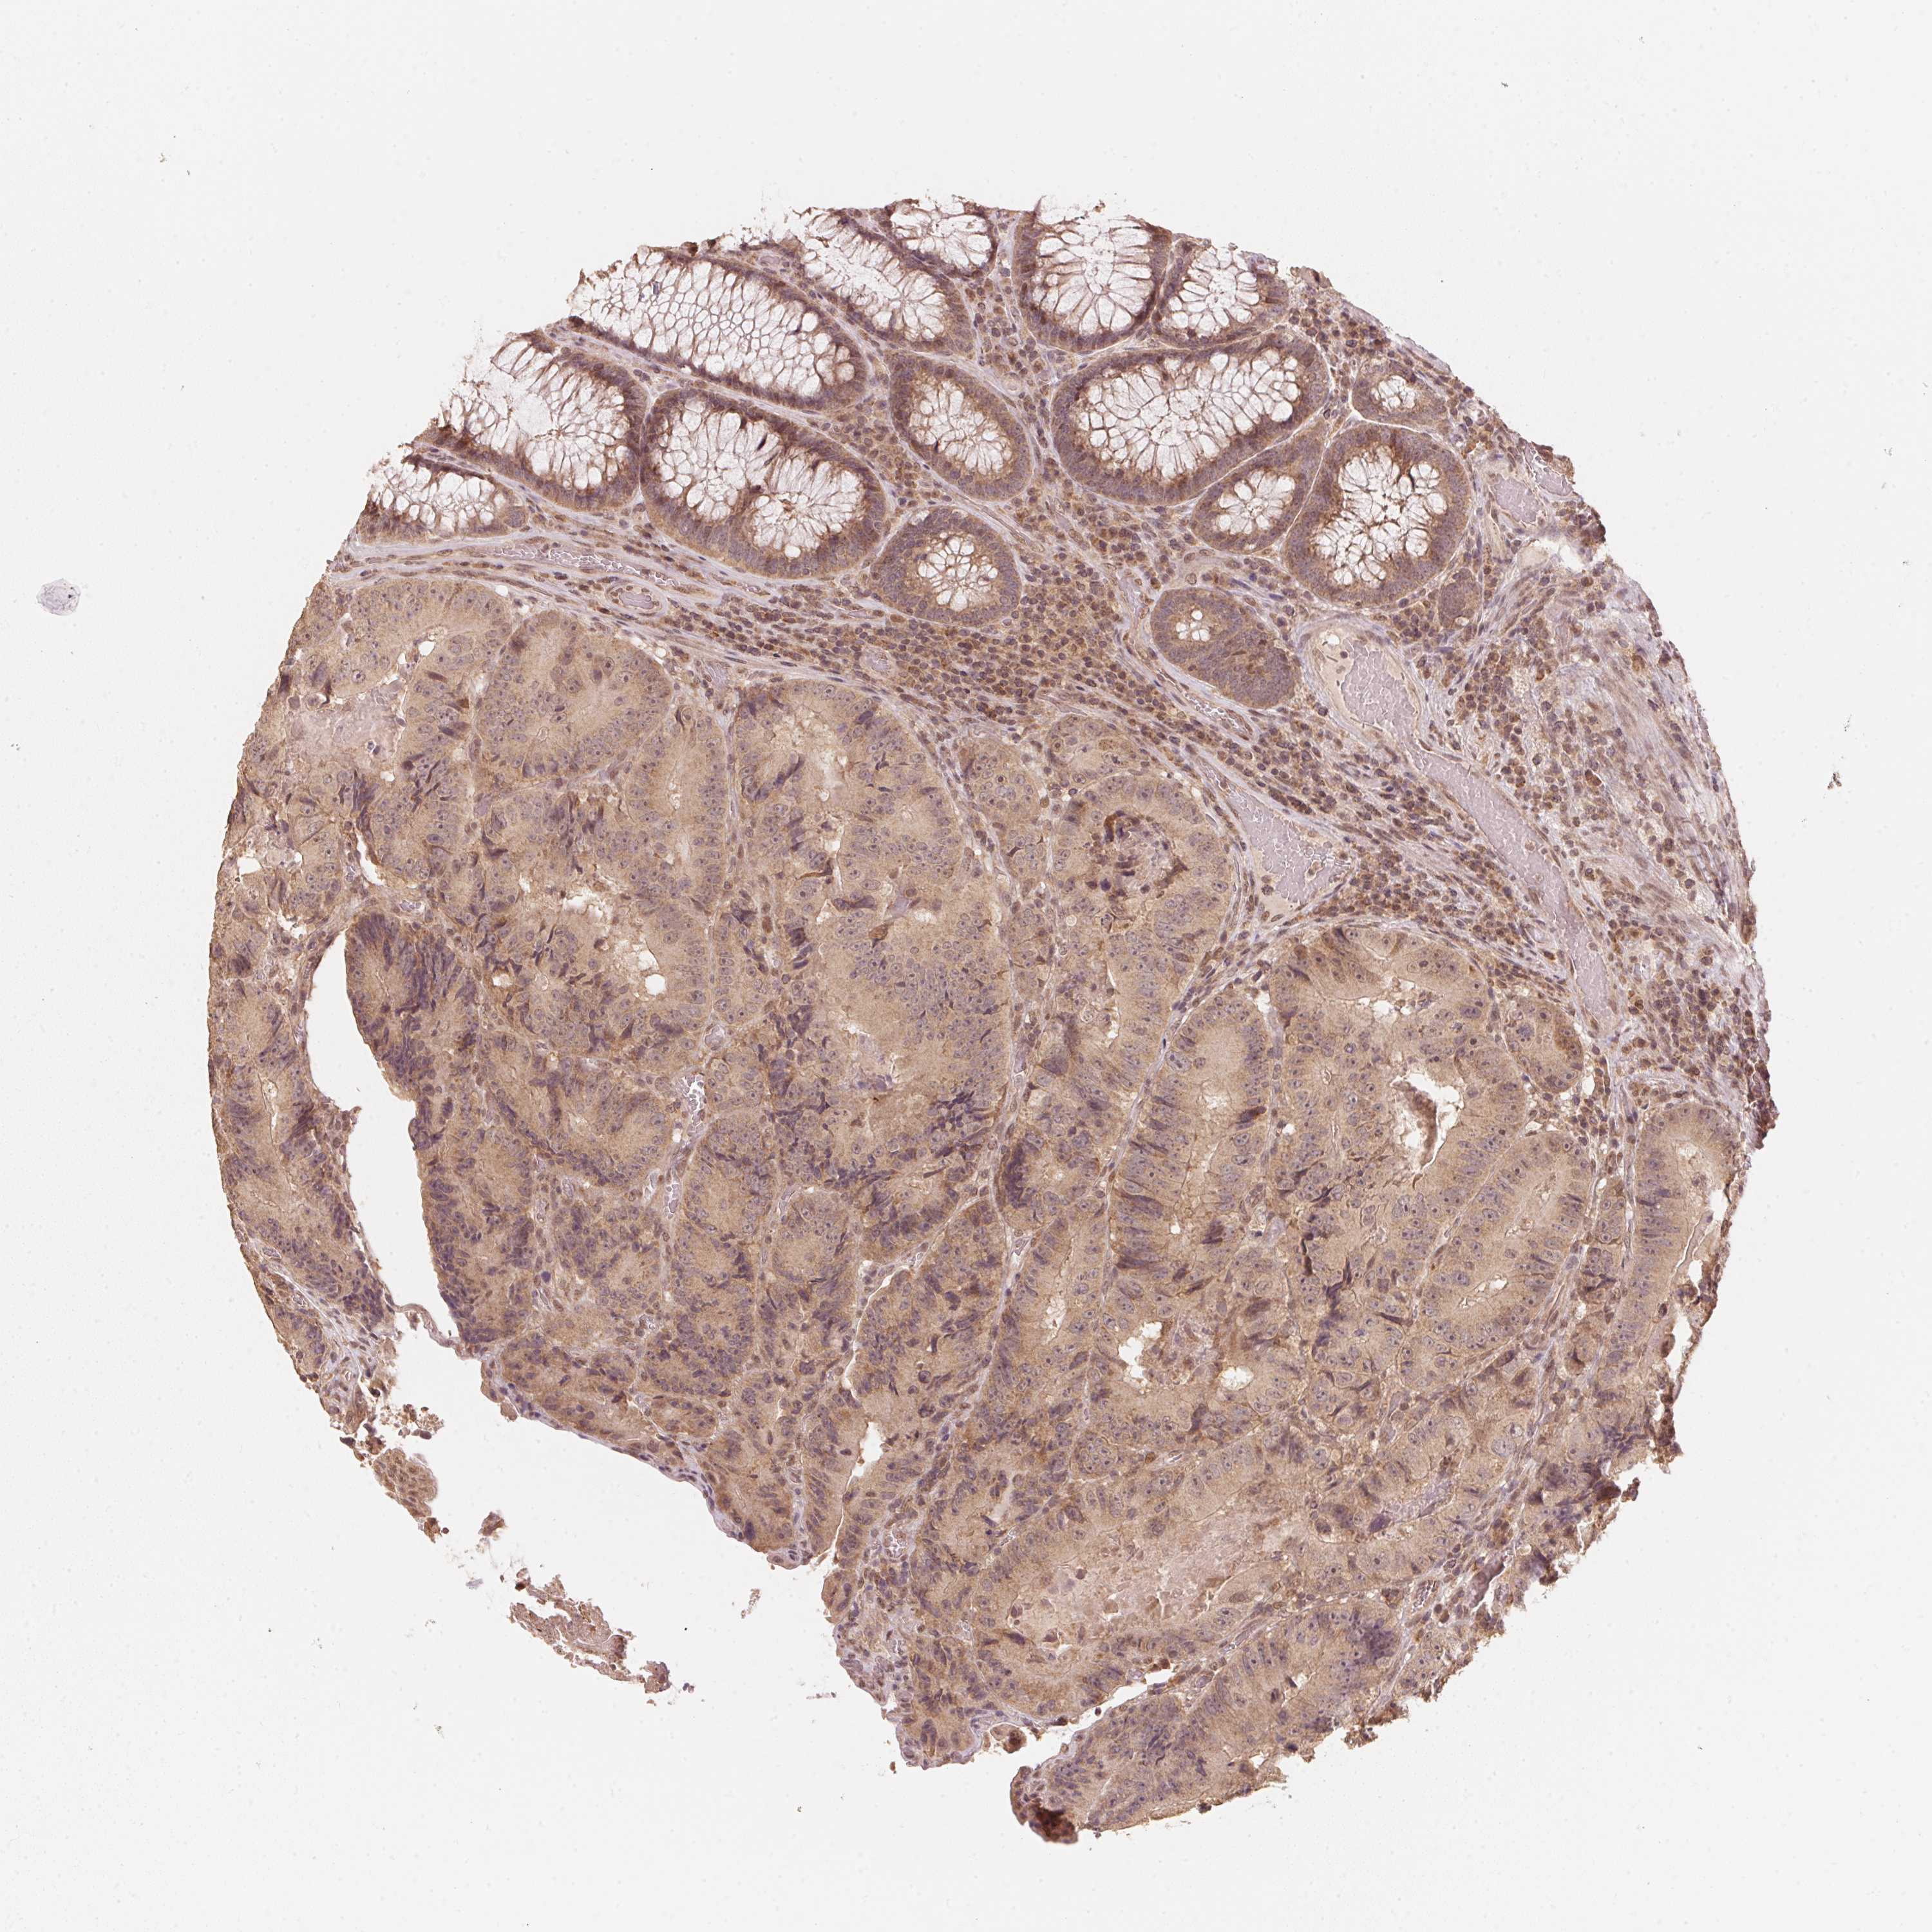

CANCER COLORECTAL CANCER Show tissue menu

Colorectal cancer

Human cancer

Rectum adenocarcinoma